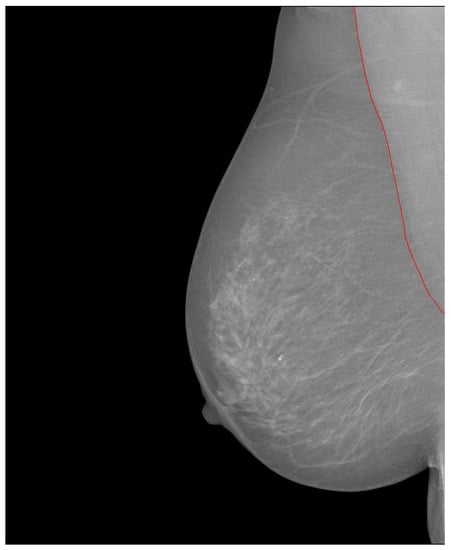

At the time of writing, the INbreast database [11] was no longer available on the official website. Mammograms in this database are stored in the DICOM format, with a resolution of either 4084 × 3328 or 3328 × 2560, depending on the breast size. The database includes images with various abnormalities such as microcalcifications, masses, architectural distortions, and asymmetries. Regions of Interest (ROIs) are defined by contour points in an XML (extensible markup language) file. Contour annotation of the pectoral muscle is also included (refer to Figure 16). Additionally, there is an extra folder that provides masks for calcifications and masses. However, it is worth noting that there are only 130 calcification masks out of 308 images with calcifications, and 107 mass masks out of 108 images with mass findings.

Figure 16. Lined contour points of the pectoral muscle. Source: [11].